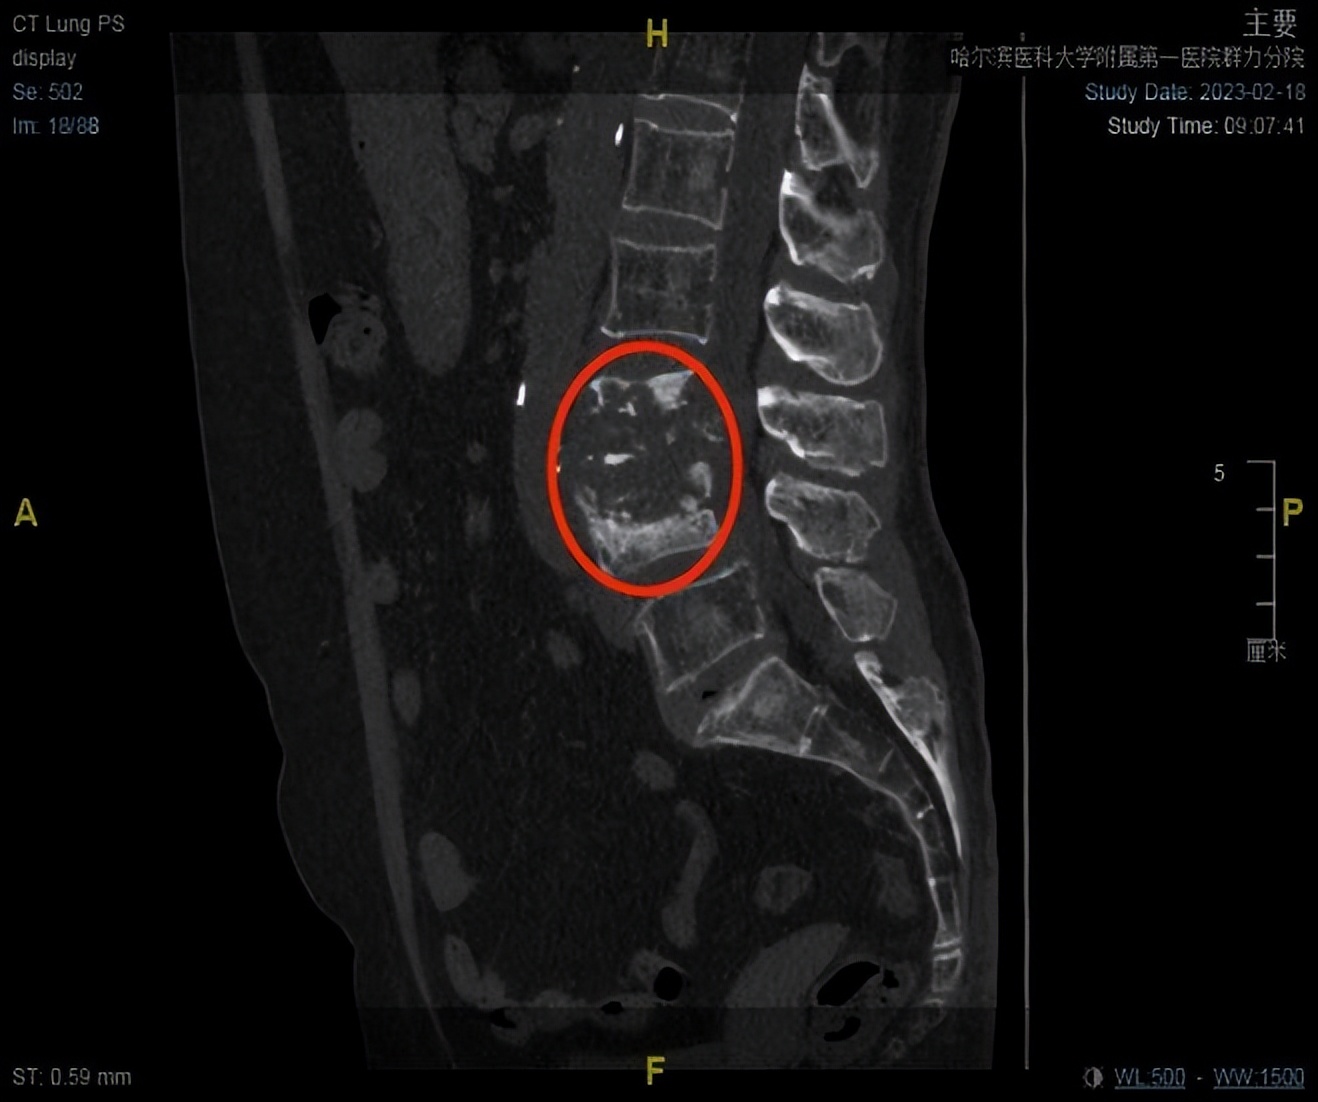

术前CT、MRI显示椎体骨质破坏,脓肿形成